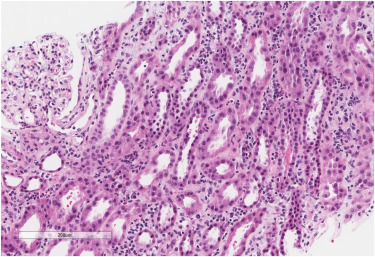

Semaglutide-Associated Acute Interstitial Nephritis: A Case Report

Source : https://www.kidneymedicinejournal.org/article/S2590-0595(22)00193-5/fulltext

Glucagon-like peptide 1 receptor agonists (GLP-1RAs) are being investigated to slow the decline of kidney function in type 2 diabetics with chronic kidney disease (CKD). These agents have proven benefits...

Conclusion: Currently, with semaglutide prescription, monitoring of kidney function is limited to patients with severe adverse gastrointestinal reactions.